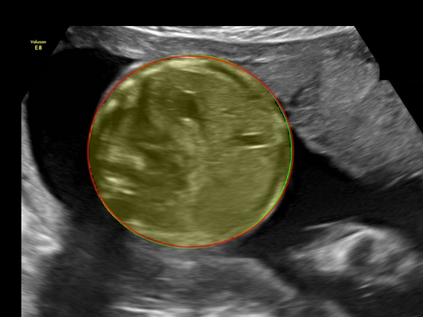

In this paper, we propose an end-to-end multi-task neural network called FetalNet with an attention mechanism and stacked module for spatio-temporal fetal ultrasound scan video analysis. Fetal biometric measurement is a standard examination during pregnancy used for the fetus growth monitoring and estimation of gestational age and fetal weight. The main goal in fetal ultrasound scan video analysis is to find proper standard planes to measure the fetal head, abdomen and femur. Due to natural high speckle noise and shadows in ultrasound data, medical expertise and sonographic experience are required to find the appropriate acquisition plane and perform accurate measurements of the fetus. In addition, existing computer-aided methods for fetal US biometric measurement address only one single image frame without considering temporal features. To address these shortcomings, we propose an end-to-end multi-task neural network for spatio-temporal ultrasound scan video analysis to simultaneously localize, classify and measure the fetal body parts. We propose a new encoder-decoder segmentation architecture that incorporates a classification branch. Additionally, we employ an attention mechanism with a stacked module to learn salient maps to suppress irrelevant US regions and efficient scan plane localization. We trained on the fetal ultrasound video comes from routine examinations of 700 different patients. Our method called FetalNet outperforms existing state-of-the-art methods in both classification and segmentation in fetal ultrasound video recordings.